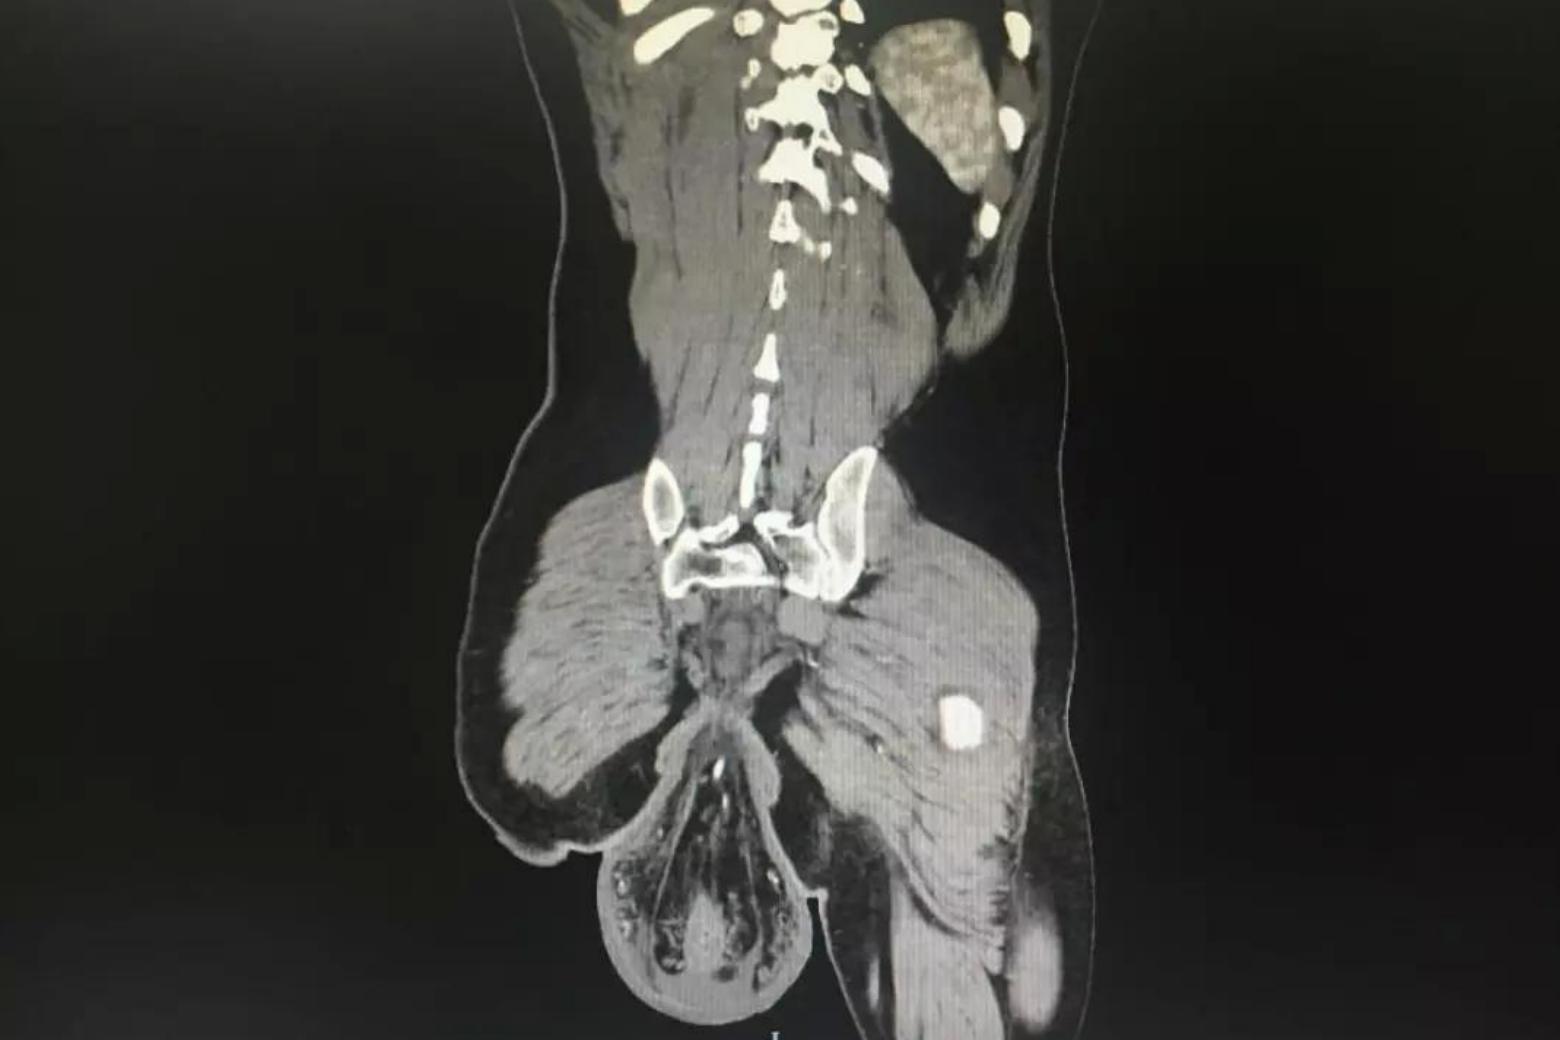

Satu gambar imbasan X-ray yang pernah tular di media sosial sekitar tahun 2018 kembali dikongsikan sebagai peringatan kepada orang ramai mengenai risiko tabiat tersebut.

Gambar itu memaparkan keadaan usus seorang lelaki yang terkeluar dari dubur akibat tekanan berlebihan ketika berada di tandas terlalu lama.

Pemeriksaan kemudiannya mendapati terdapat ketulan sebesar bola yang terkeluar dari duburnya.

Doktor mengesahkan ketulan tersebut adalah rektum, iaitu bahagian akhir usus besar, yang terkeluar dari tempat asalnya. Keadaan ini dikenali sebagai rektum prolaps (rectal prolapse).

Imbasan CT menunjukkan ketulan itu berdiameter lebih 15 sentimeter, selain terdapat kesan lebam dan pendarahan pada dinding usus.